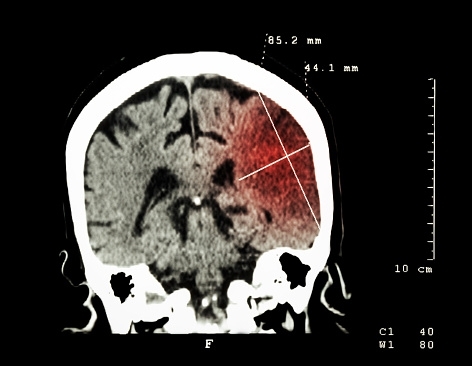

De son acronyme AVC, les Accidents Vasculaires Cérébraux font dorénavant partie des maladies qui font peur à la plupart de nous. Entre 2002 et 2012, le nombre de patients hospitalisés dus aux AVC a augmenté de 16%.

En Europe, 1 400 000 personnes sont concernées par cette maladie, des chiffres qui deviennent de plus en plus inquiétants. Une question se pose : est-il possible de prévenir les AVC ? Et la réponse est probablement OUI.